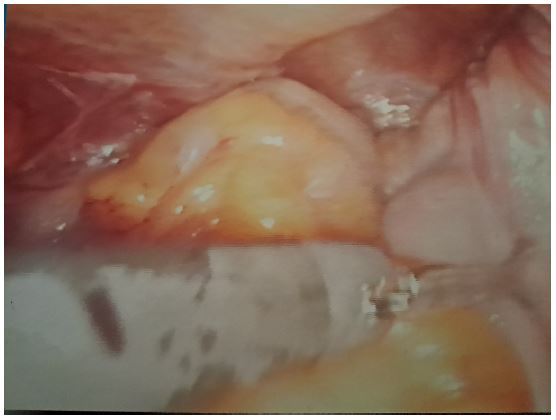

Figure 4: Hernia sac.

Images are not display check it